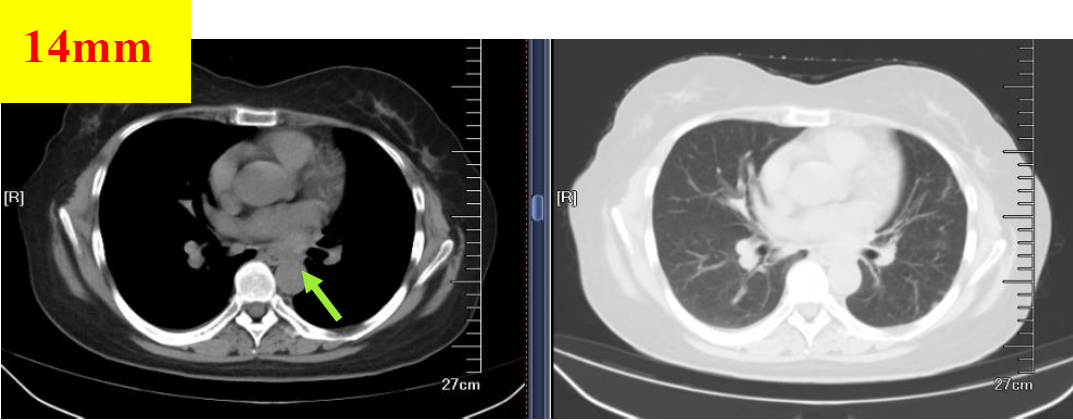

图3 2018.08.28影像学检查(PR)

图4 2018.09.27影像学检查(PR)